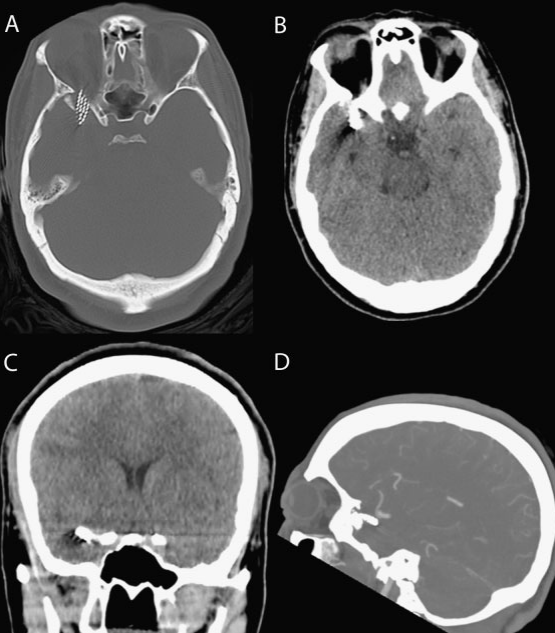

НемедицинаFigure 1. Предоперационная компьютерная томография (КТ) и компьютерно-томографическая ангиография (КТА) с повреждением правой средней ямки зубной щеткой.

(А) Аксиальная компьютерная томография с переломом правой клиновидной кости, на которой видны щетинки зубной щетки. (Б) Аксиальная компьютерная томография, на которой видна головка зубной щетки в передней части височной доли. Сопутствующего кровоизлияния не обнаружено. (В) Коронарный снимок, демонстрирующий кончик зубной щетки рядом с передним клинообразным отростком. (Г) Боковая компьютерная томография показывает близость инородного тела к бифуркации правой средней мозговой артерии (СМА).